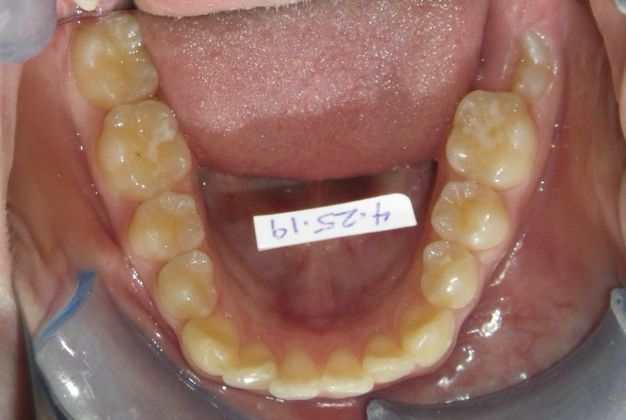

Orthodontics: Case 34

This patient had an upper right permanent cuspid that was impacted and would need uncovering by oral surgeon who would place bracket with chain to help enable us to tease the permanent cuspid into its proper position. She also had a permanent 2nd Molar that was impacted due to improper development of 3rd molars and the oral surgeon could remove them at the same time as uncovering of the permanent cuspid. After uncovering and removal of lower 3rd molars, we would begin comprehensive straight wire orthodontic treatment.